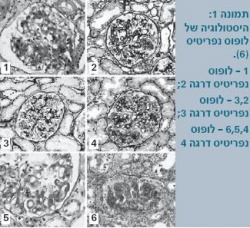

ארגון הבריאות העולמי (WHO - World Health Organization) הגדיר סיווג מורפולוגי המבוסס על ביופסיה כלייתית (תמונה 1), שעודכן בשנת 2003 על ידי החברה הבין-לאומית לנפרולוגיה ופתולוגיה כלייתית[6]. טווח הסיווג ההיסטולוגי הוא מכליה נורמלית במיקרוסקופ אור (דרגה 1) עד דלקת כליה טרשתית מתקדמת (דרגה 6) (טבלה 3).

במקרים קיצוניים ניתן לחזות את דרגת הסיווג המורופולוגית, בייחוד כאשר החולה מתייצג עם מספר אפיזודות של אי ספיקה כלייתית קשה ויתר לחץ דם משמעותי. עם זאת, במקרים קלים יותר קשה לחזות את רמת הפגיעה הכלייתית על בסיס מאפיינים קליניים ומעבדתיים.

ראוי לזכור כי גם מטופלים עם דלקת כליות בדרגה הגבוהה ביותר יכולים להיות בשלבים הראשונים של המחלה עם תפקוד כלייתי תקין וערכים תקינים של לחץ דם. בכל התייצגות עם אי ספיקה כלייתית, הפרעה בתפקודי הכליה או משקע שתן פתולוגי יש לבצע ביופסיה כלייתית כדי לבסס את הסיווג שעל פיו יוחלט על טיפול.

רוב הנגעים (לזיות) המשמעותיים כרוכים במשקעים תת-אפיתליאליים נרחבים ושגשוג (פרוליפרציה) של המזנגיום (Mesangium). רוב המטופלים המפתחים אי ספיקת כליות סופנית הם בדרגות 3 או 4 לפי ביופסיה.

דרגה 2 מצביעה על מחלה קלה יחסית, הדורשת טיפול מועט ביחס לדרגות הגבוהות יותר, עם שרידות גבוהה יותר ותפקוד כלייתי מצוין. ב-20-30% מהמקרים, עם זאת, חולים יכולים לעבור התמרה לדרגות 3 או 4 אחרי חודשים ואף שנים. במקרים אלו הישרדותם של החולים והתפקוד הכלייתי שלהם זהים לאלו שאובחנו מלכתחילה בדרגות 3 או 4[7] [8].